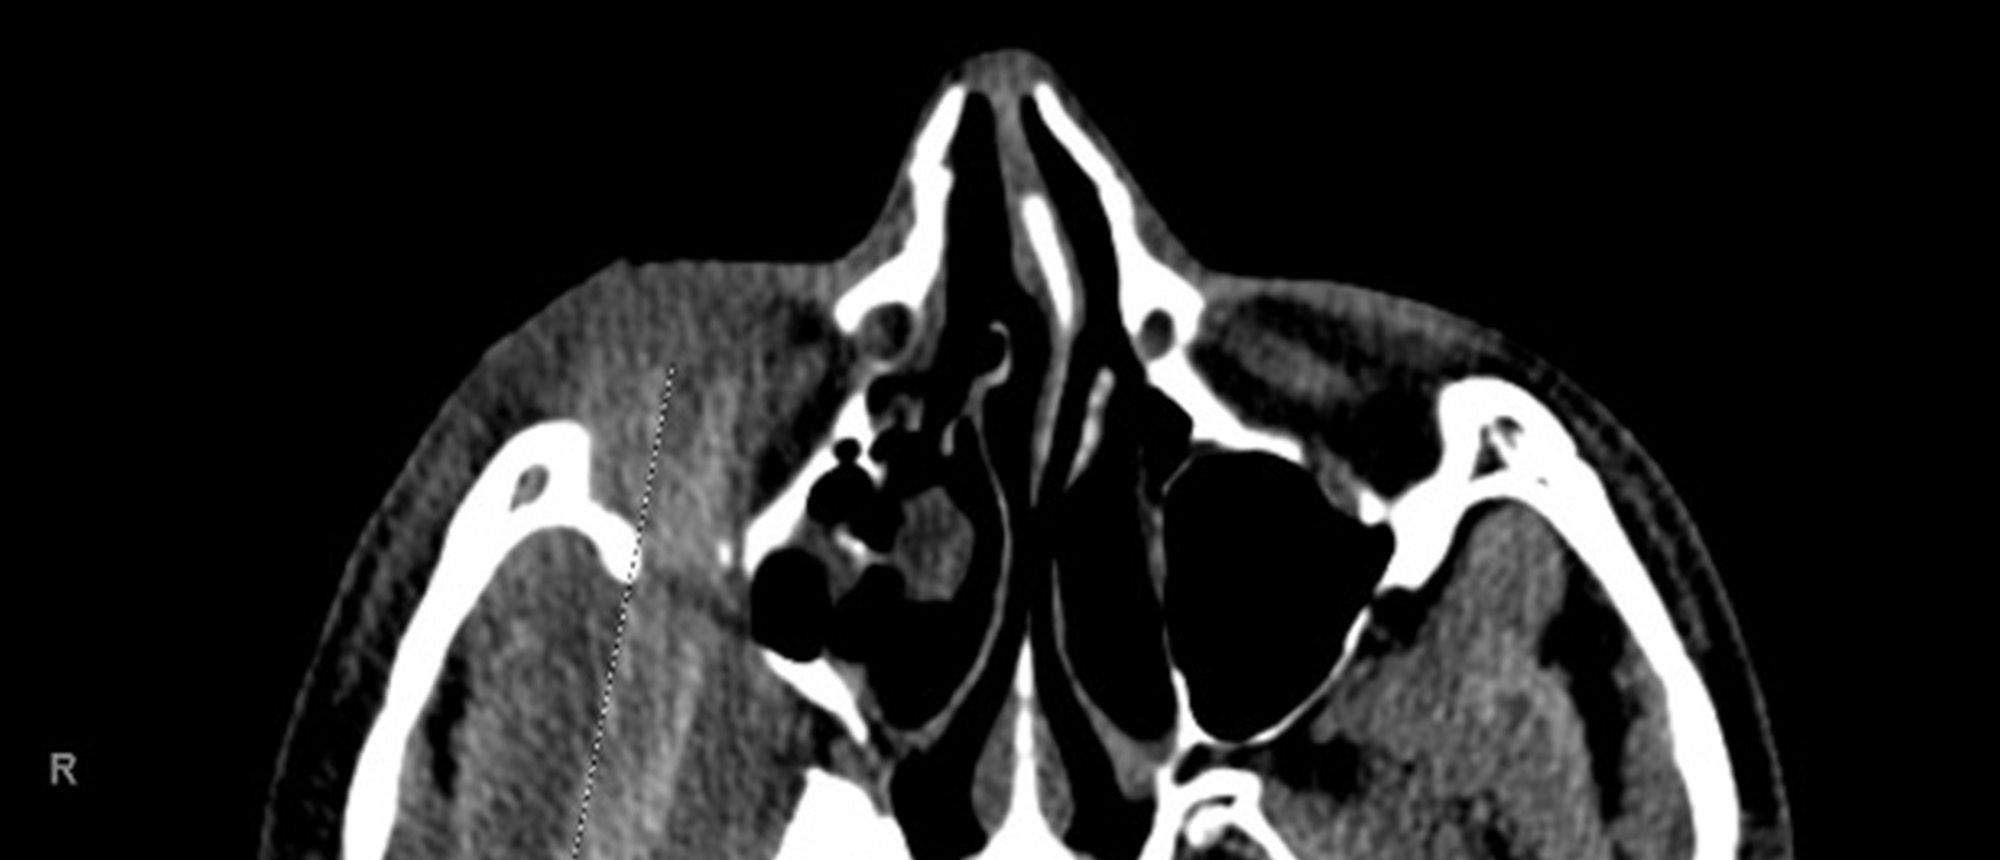

Abstract A patient presented with several weeks of right eye proptosis. On initial examination, his visual acuity in the right eye was 20/400, and a relative afferent pupillary defect was noted. He had 4 mm relative proptosis on the right and restricted motility in all gaze directions. CT orbits re…

NUT Carcinoma

NUT Carcinoma A patient presented with several weeks of right eye proptosis. On initial examination, his visual acuity in the right eye was 20/400, and a relative afferent pupillary defect was noted. He had 4 mm relative proptosis on the right and restricted motility in all gaze directions. CT orbi…